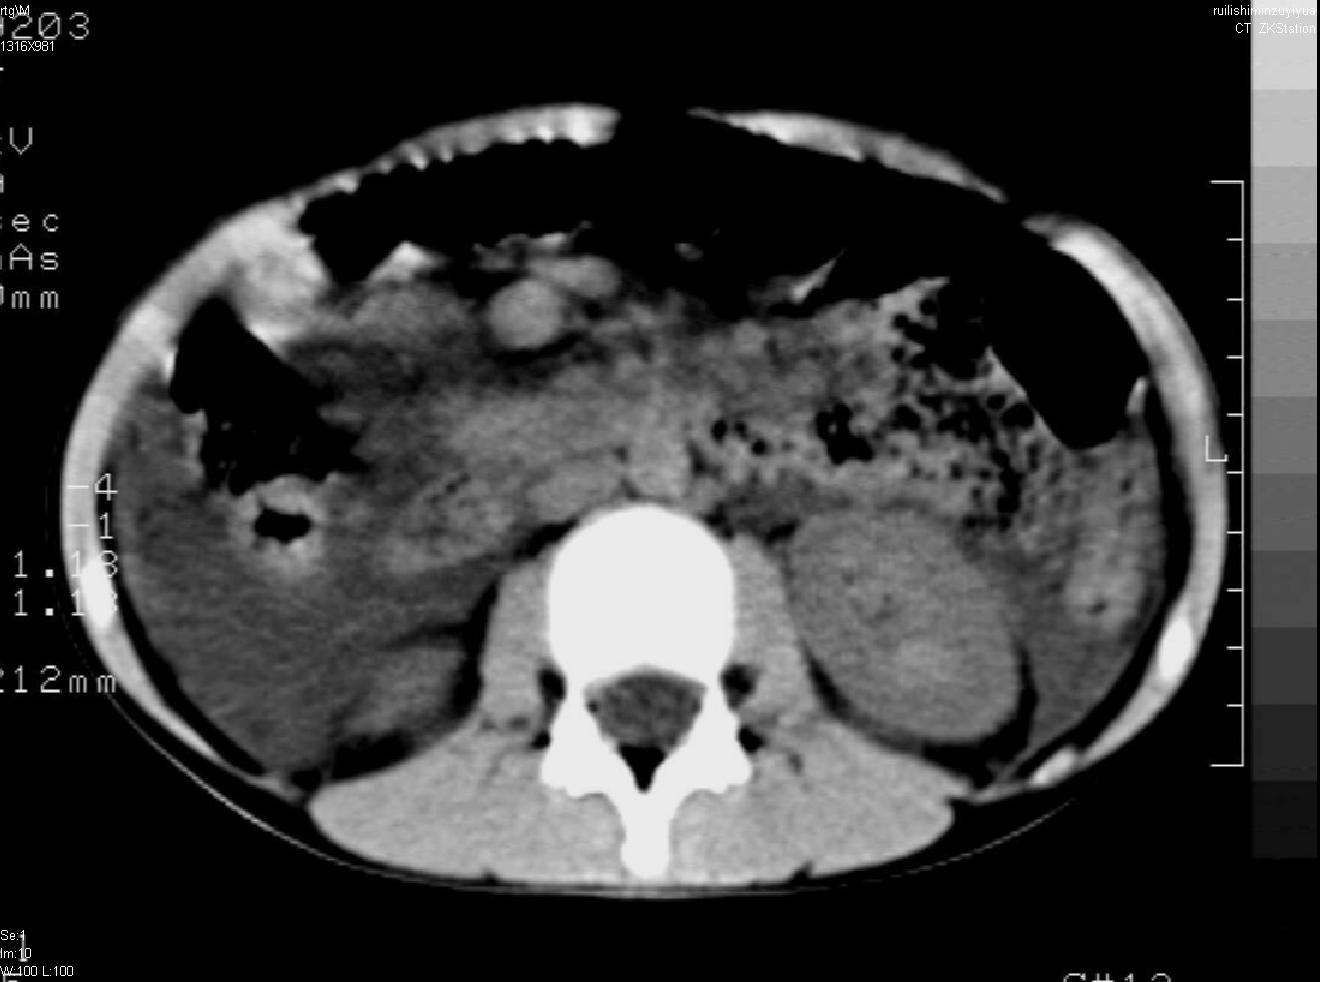

标题: PED0282:女,10岁,上腹疼痛2周 [打印本页]

标题: PED0282:女,10岁,上腹疼痛2周

b超:胆囊结石。疑坏死性胰腺炎

支持小儿急性坏死性胰腺炎。

2.出血坏死型胰腺炎  约占10%~20%,病变急剧,因缺血、出血或坏死,胰腺呈深红色或紫黑色,大量渗出液包含胰液流入腹腔而引起弥漫性腹膜炎,可发生休克,甚至死亡。此时富有消化力的胰液渗出,作用于脂肪丰富的大网膜、肠系膜等,造成广泛脂肪坏死灶,将脂肪分解为甘油和脂肪酸。后者又吸取血中钙质形成钙化灶。血钙可显著降低而出现手足搐搦现象。

早期并发症包括水和电解质紊乱,低钙血症和手足搐搦。后期可并发症腺脓肿,假性囊肿形成,亦可遗留慢性胰腺炎。

支持急性胰腺炎并腹膜炎。

急性胰腺炎,腹腔积液